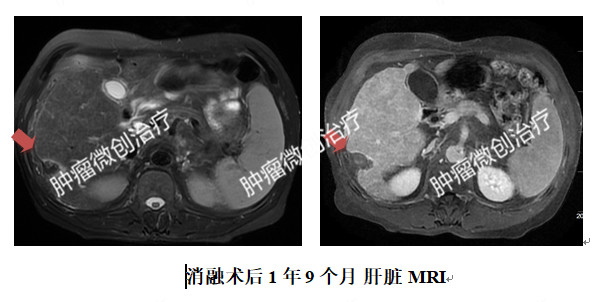

经过充分准备,李大爷接受了冷冻消融治疗。整个过程约1小时,术后即刻CT扫描可见冰球覆盖目标病灶,范围约4.5cm×4.5cm×5.9cm,未影响周围组织、器官。

术后复查,肿瘤坏死完全,达到外科手术切除效果。术后至今,李大爷恢复了正常的生活。